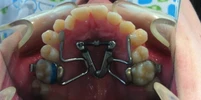

Çene Problemleri

Çene Bozukluğu

Diş Çene ve Yüz Bölgesi Gelişim Yetersizlikleri

Ortodonti